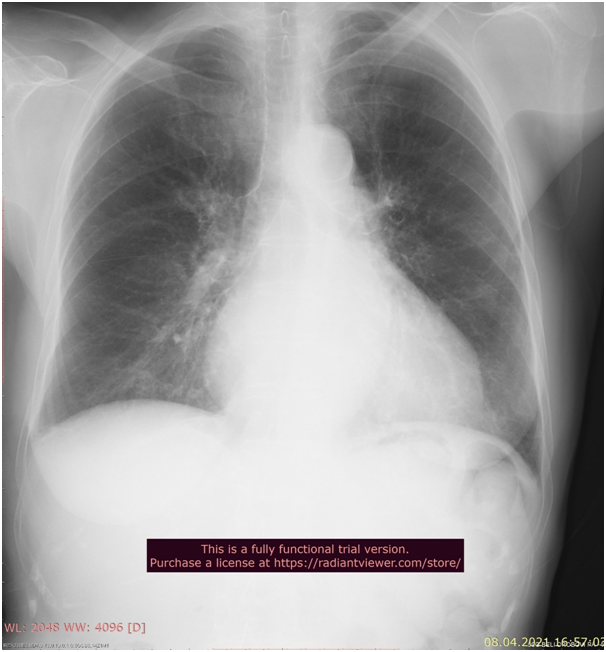

In this study we have 7 COVID positive patients from our hospital in time period from 18 November 2020 to 21 April 2021, four male and three female patients. Six of them had surgery intervention but only one was treated conservatively, because of the diagnosis of acute pancreatitis. Three of the Covid patients were admitted by abdominal surgeon, three of them were admitted by trauma surgeon and one of the patients were admitted by vascular surgeon. Before the surgical intervention we tested the patients and all of them had PCR test positive. When we analyze symptoms three patients were asymptomatic and four of them had COVID 19 related symptoms-dyspnea with low saturation and fever. Four symptomatic patients had COVID 19 pneumonia on RTG and one symptomatic patient had COVID 19 pneumonia on CT lungs. On laboratory analysis four of the patients show lymphocytopenia, low serum iron levels, high level of CRP and D-dimer. Six of the patients who went to surgical intervention, were treated with antibiotics and anticoagulant therapy. Patients who went to abdominal surgery had diagnosis of liver echinococcosis and adhesive ileus, but the third patient was with acute pancreatitis and was treated conservatively. Patients who went to trauma surgery had diagnosis of hip fracture, another patient had hip fracture and pedal skin necrosis and third patient was with radial fracture. Patient admitted on vascular surgery had diagnosis of gangrene caused by diabetic angiopathy. Three patients who were operated by trauma surgeon had successful operation, two of them were released home after few days, and the third female patient who was elderly (80year old) and despite RTG lung with signs of COVID 19 pneumonia, she remained asymptomatic and was transferred to geriatric hospital in stable condition. Patients who were with COVID pneumonia were treated with antibiotics, anticoagulant therapy and three patients who had low saturation were treated with oxygen supply and intravenous corticosteroid therapy. Two patients with COVID 19 pneumonia died from acute respiratory insufficiency and one died from cerebrovascular insult. The patient with acute pancreatitis who was conservatively treated, COVID 19 pneumonia was  diagnose by CT thorax, but the clinical condition worsened and she was transferred to COVID hospital. One of the abdominal patient with diagnose of adhesive ileus  who died from acute respiratory insufficiency had comorbidities DM type 2, St post PCI/Stenting LAD et RCA, St post CVI, and the vascular patient with gangrene and  diabetic angiopathy had comorbidities St post CABG, atherosclerosis generalized and he was the second patient who died from acute respiratory insufficiency, with low O2 saturation 68% and high levels of urea and creatinine in blood, despite being  treated with corticosteroid therapy, oxygen supply, anticoagulant therapy and antibiotics. Female patient with the diagnosis of liver echinococcosis was the third patient who had complication of COVID-19 infection cerebrovascular insult and died from that complication. She had only arterial hypertension as comorbidity (Figures 1 & 2).

Figure 1 Rtg of lungs in 80 old female asymptomatic patient with Covid 19-pneumonia.